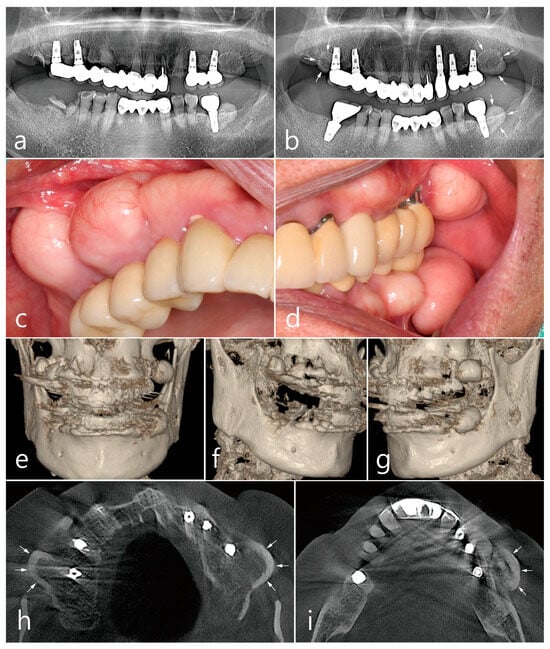

Panoramic radiography performed at the first visit showed that the implants were placed in both the posterior maxillary regions and the first molar of the left mandible. The patient reported that the implants had been loaded for 7 years. Both prostheses in the posterior maxilla were cement-type three-unit bridges and a single screw-type crown was delivered in the left posterior mandible. An assessment of the prostheses showed no specific occlusal overloads or interferences in the posterior implants. Ovoid radiopaque masses were observed in the posterior alveolar ridges where the implants were placed (Figure 1a). The proliferating mass in the maxilla showed a radiolucent medullary space within the outer cortical layer, and the mass in the mandible showed radiopacity with uniform bone density. The root rests of the left maxillary canine and right mandibular first molar were extracted and replaced with dental implants. After 1 year of prosthetic loading on the two additional implants, the panoramic view showed a more pronounced radiopaque mass in the three previous areas (Figure 1b).

Prominent dome-shaped masses were observed during the patient’s intraoral clinical examination (Figure 1c,d). The patient experienced difficulties with tooth brushing and mastication. The patient said that he was not aware of the appearance of the bone mass when the implant was first placed and that he was able to recognize it only after it grew over time. No paresthesia or tenderness was associated with the lesion, and the regional lymph nodes were not palpable. Based on clinical and radiological findings, the bone mass in this case was diagnosed as PO. The implant adjacent to the PO was accompanied by peri-mucositis, and peri-implant bone loss with thread exposure was observed in the left maxillary first molar implant. Proliferating, well-circumscribed, and pedunculated masses were clearly observed in the 3-D cone-beam computed tomography (CBCT) (Figure 1e–g). On the axial CBCT image, the PO proliferated from the buccal bone of each maxillary posterior region (white arrows) (Figure 1h). The mass was lined with a dense external cortical layer and internal radiolucent bone marrow. PO of the buccal bone of the left mandibular posterior implant (white arrows) showed a dense and thick outer cortical layer and a relative lack of bone marrow space (Figure 1i).

The removal of the PO in the right posterior maxilla was planned 2 months after surgery in the left quadrant. Multiple POs arising from the buccal alveolar ridge adjacent to the posterior implant were observed (Figure 5a). After the flap was reflected, three isolated POs were observed (Figure 5b) and removed via osteotomy at the base of the pedunculated masses. The exposed surface was smoothened using a bone file (Figure 5c). The size of the largest specimen was approximately 1.5 × 1.0 × 1.0 cm (Figure 5d). Histologically, the specimen was a cancellous PO with a wide medullary space filled with fatty and loose connective tissue surrounded by a compact cortical layer (Figure 5e,f). A well-healed surgical site was observed after 1 year of follow-up (Figure 5g). No signs of recurrence were found in the clinical and radiographic images taken 1 year after surgery (Figure 6a,b).

Figure 1. Preoperative examinations. Panoramic radiography (a) at the first visit, and (b) at one year after two additional dental implants at the maxillary left canine and mandibular right first molar. Ovoid-shaped radiopaque mass (white arrows) shown in the posterior ridges of both the maxilla and left mandible; (c,d) multiple proliferated round-shaped osteomas observed in the posterior ridges; (e) proliferated, well-circumscribed, and pedunculated masses observed in the 3-D images of CBCT; (f) a 3-D image of peripheral osteoma (PO) in the maxillary right posterior area; (g) a 3-D image of PO occurred in the upper and lower left posterior area; (h) an axial image of CBCT showing the proliferated bone mass in the buccal bone of the maxillary posterior implant (white arrow). Mass having external cortical layer and the internal radiolucent marrow space; (i) proliferated bone mass in the buccal bone of the mandibular posterior implant (white arrow).

Figure 6. Examination after one year of the surgery. Panoramic view (a) and intraoral clinical view (b) showing no recurrence of PO.